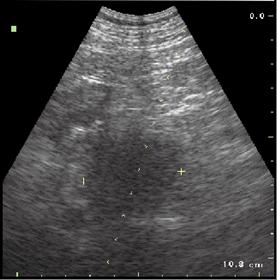

Под

сонографическим контролем при подозрении на новообразование ПЖ пункционный

материал взят в 340 случаях. Пункционная биопсия объемных образований

выполнялась под местной или общей анестезией (рис. 4.7.1). После выбора

траектории пункции и обработки операционного поля, под непрерывным УЗ-контролем

выполняется послойная инфильтрация тканей раствором анестетика.

Рис. 4.7.1. Б-ной С. Диагноз: Опухоль головки ПЖ. ТАУЗИ, косое продольное сканирование, биопсия. (ткань опухоли головки ПЖ; ДПК; раектория иглы).